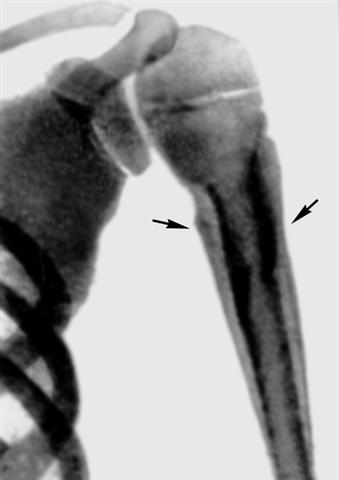

Рис. 2. Рентгенограмма плечевой кости ребенка 10 лет при хроническом остеомиелите в стадии обострения (прямая проекция): линейные тени периостальных наслоений (указаны стрелками) в проксимальном отделе плечевой кости.